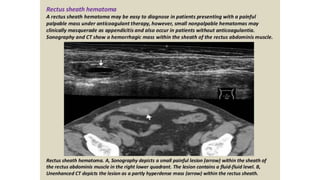

This document discusses the evaluation of right lower abdominal pain and lists appendicitis as a key cause. It notes that other potential causes include hemorrhagic cysts, heterotrophic pregnancy, salpingitis with pyosalpinx, funiculitis, and torsion of an undescended testis. The document was presented by Dr. A.S.M. Sufian of Cumilla Medical College Hospital and thanks the audience for their patience and listening.